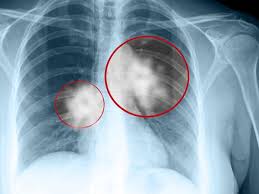

U trung thất là một khối u bất thường xuất hiện ở vùng trung thất của cơ thể, gây ra nhiều biến chứng và ảnh hưởng đến sức khỏe của người bệnh. Việc điều trị u trung thất phụ thuộc vào nhiều yếu tố như vị trí, kích thước và tính chất của khối u. Dưới đây là những thông tin cần biết về điều trị u trung thất.

U trung thất cần được điều trị sớm vì nếu không can thiệp, khi khối u phát triển, chúng sẽ chèn ép các cơ quan và mô. Các khối u trung thất nếu không được điều trị có thể phát triển nhanh gây ảnh hưởng nghiêm trọng đến sức khỏe người bệnh. Bệnh nhân dù có bị u trung thất lành tính hay ác tính thì đều có nguy cơ gặp biến chứng nếu không được điều trị kịp thời. Phần lớn những khối u phát triển trong trung thất đều được chỉ định áp dụng kỹ thuật sinh thiết, cắt bỏ, hoặc điều trị bằng xạ trị, hoá trị nếu phát hiện đó là các tế bào ung thư. Phẫu thuật là biện pháp điều trị cơ bản cho các khối u trung thất, đặc biệt khi có dấu hiệu chèn ép và xảy ra biến chứng, ảnh hưởng đến đường thở của bệnh nhân.